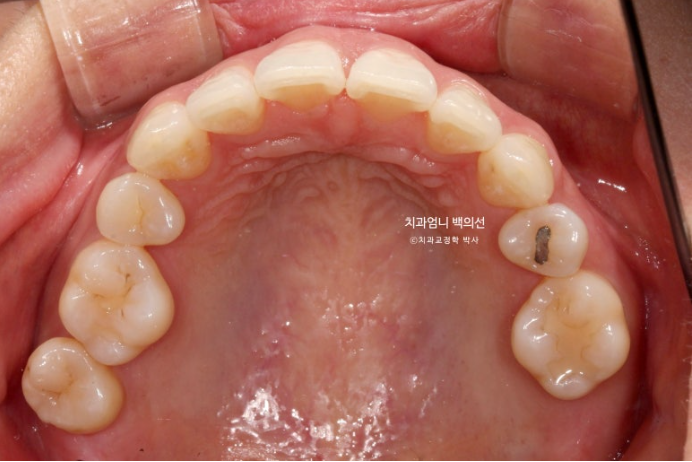

23.08

엑스레이상 좌측 위 첫번째 작은어금니 쪽으로 두번째 작은어금니가 쓰러지며 공간이 없어진게 보입니다.

어금니 교합관계 2급 입니다.